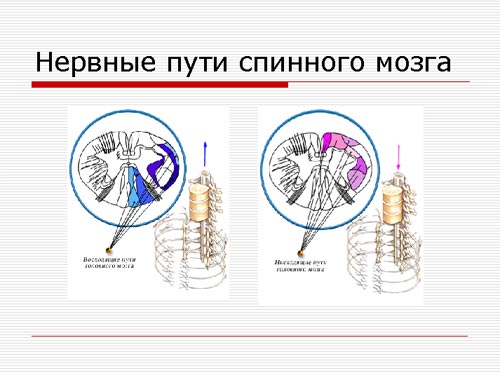

Проводящая и рефлекторная функция спинного мозга. Расположение нисходящих и восходящих нервных путей, коленный рефлекс.

На рисунке мы видим нервные пути спинного мозга

Рис. 4. Нервные пути спинного мозга.